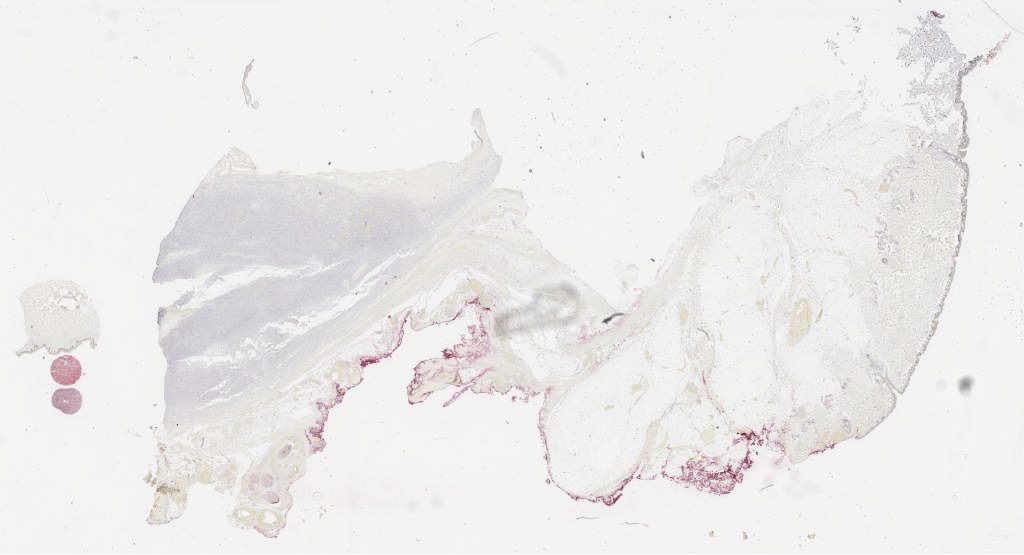

he.svs

105575

85739

40X